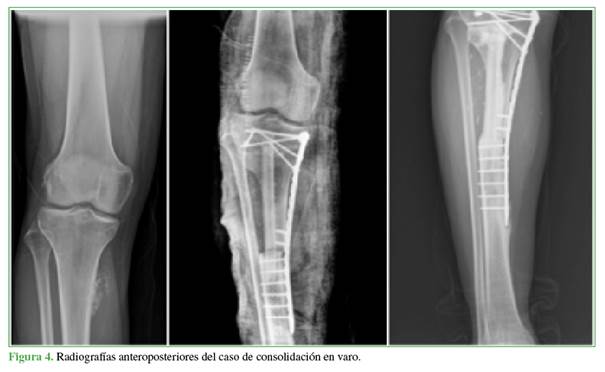

Concretamente, el injerto vascularizado de peroné es el colgajo microvascular óseo más utilizado debido a su gran versatilidad para las reconstrucciones, ya que permite montajes únicos, con doble barra o asociando colgajos musculocutáneos para solventar defectos de cobertura.2,3 Todas estas opciones hacen posible que se pueda utilizar en defectos que miden desde 5 cm hasta 25 cm, siempre que se respeten los últimos 7 cm distales y 4 cm proximales de peroné para evitar complicaciones en la zona donante (Figura 1).

El seguimiento clínico y radiológico fue mensual, trimestral, semestral y anual en función de la evolución del paciente, por un período mínimo de dos años. En una radiografía simple, se evaluó la consolidación ósea completa para huesos donante y receptor después de la cirugía.